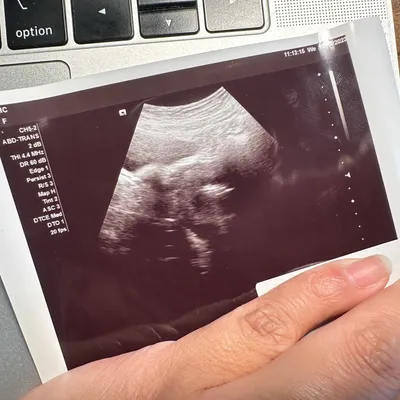

寶寶第 31 週的成長狀況

您的寶寶現在大約一顆椰子的大小,重約1.5公斤,從頭到腳的身長約40公分。

到目前為止,寶寶每天將大約250毫升尿液排入羊水中,同時也會吞嚥羊水,而羊水每天會完全地更換好幾次。若羊膜囊中有多餘的液體,可能意味著寶寶沒有正常吞嚥,或有胃腸道阻塞的問題。若是羊膜囊中的液體不足,則表示嬰兒可能沒有正常排尿,或是腎臟或泌尿道有問題。醫師會在做例行超音波檢查時,也測量您的羊水量。